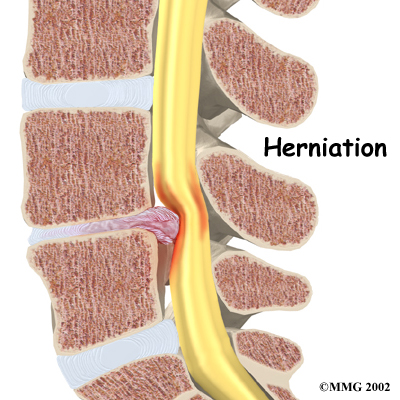

Disc herniation: Spinal stenosis can occur when an intervertebral disc in the low back (ruptures). Normally, the shock-absorbing disc is able to handle the downward pressure of gravity and the strain from daily activities. However, if the pressure on the disc is too strong, such as landing from a fall in a sitting position, the nucleus inside the disc may rupture through the outer annulus and squeeze out of the disc. This is called a disc herniation. If an intervertebral disc herniates straight backward, it can press against the nerves in the spinal canal, causing symptoms of spinal stenosis.